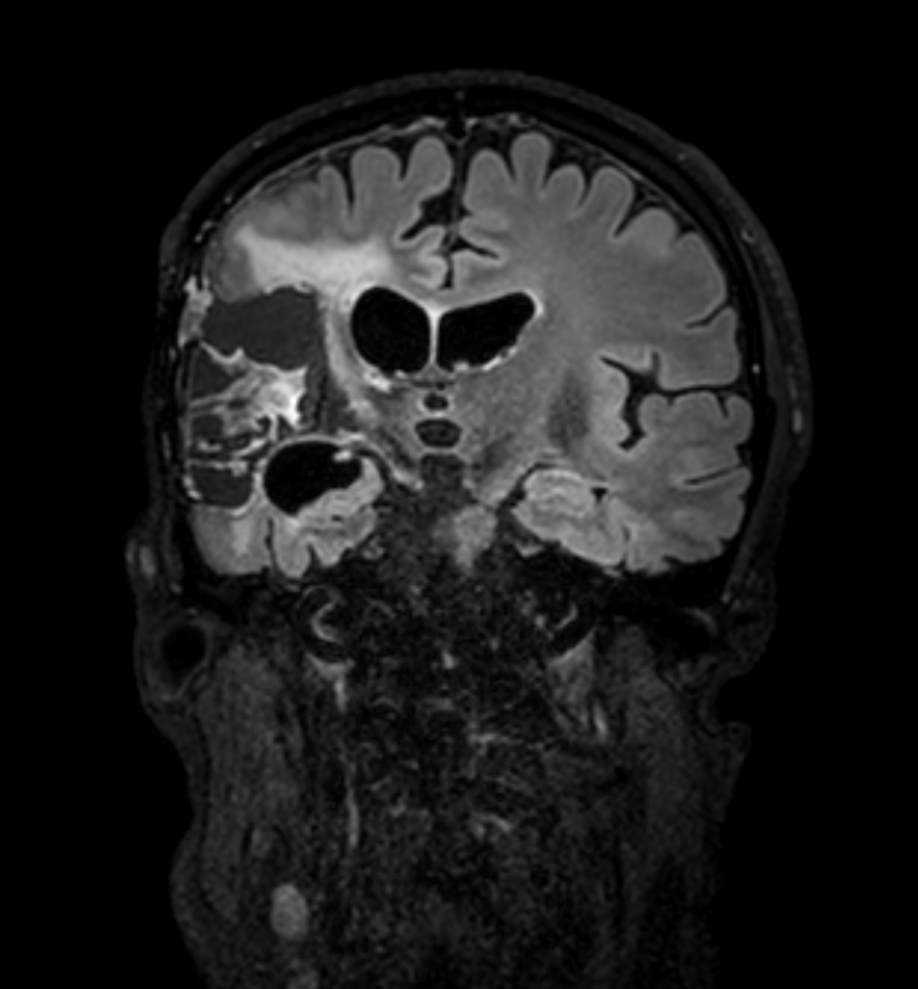

Brain glioblastoma, post-operative

Patient who was operated on glioblastoma

3D FLAIR - Coronal reformat